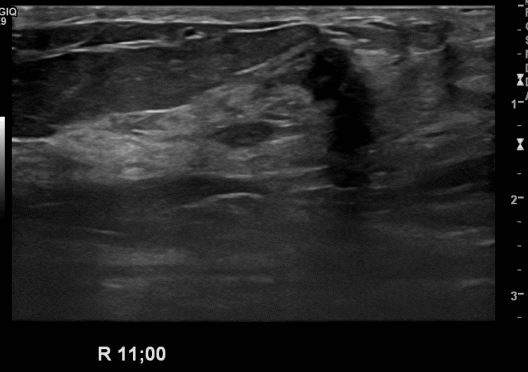

상기환자 건강검진상 이상소견으로 내원하신 50대 여성분으로 본원 초음파상

우측유방 11시 방향에 의심스러운 멍울 조직검사 시행하여 우측 침윤성 소엽암

진단되었습니다.